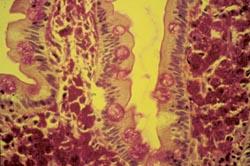

In der Darmschleimhaut werden die Immundefizienzviren vorwiegend in einer Untergruppe von Lymphozyten, den CD4-positiven Helferzellen, und in Makrophagen (Fresszellen) gefunden. Weiter konnten wir zeigen, dass parallel zur starken Vermehrung der Immundefizienzviren in der Darmschleimhaut der Verlust der wichtigen immunregulatorischen Helferzellen (CD4-positiven T-Zellen) im Darm viel früher als im Blut einsetzt und, wie wir im Tiermodell nachprüfen konnten, bereits 14 Tage nach Infektion fast vollständig ist. Diese dramatischen Störungen im spezialisierten Darmimmunsystem führen zur Ausbreitung sonst eher harmloser Durchfallerreger, wie z. B. dem Protozoon Cryptosporidium parvum (Abbildung 2). Eine solche Infektion kann schließlich zum Tode des Patienten führen. Neben diesen Infektionen im Verdauungstrakt kann es auch schon sehr früh zu Veränderungen im Aufbau der Dünndarmschleimhaut, die für die Aufnahme von Nahrungsbestandteilen verantwortlich ist, kommen. Bei Betrachtung der Feinstruktur fällt eine Abflachung der Dünndarmzotten nach HIV- und SIV-Infektion auf (Abbildung 3). Diese so genannte Zottenatrophie ist auch funktionell wirksam, da im Verlaufe der Infektion bestimmte Vitamine und Spurenelemente vermindert aufgenommen werden. Diese Beobachtungen führten zur Prägung des Begriffs der HIV-Enteropathie und könnten unter anderem den schlechten Ernährungszustand der AIDS-Patienten erklären.

Abbildung 5: Unter dem Mikroskop kann man innerhalb der Dünndarmzotten viele rot gefärbte Strukturen erkennen, die den Bakterien (Tropheryma whippelii) entsprechen. |